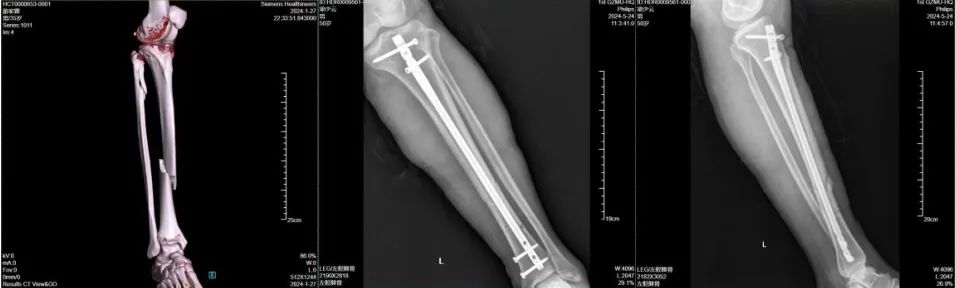

47岁的刘女士(化名),今年在工作时右臂意外遭到重击受伤,拍片发现右肱骨、桡骨远端骨折,严重影响工作和生活,来到广医一院横琴医院就诊。 在广医一院横琴医院骨科副主任医师闫伦春门诊就诊发现其右肱骨骨折、右桡骨远端骨折,闫伦春副主任医师团队为其行“右肱骨骨折闭合复位髓内钉内固定术+右桡骨远端骨折切开复位钢板螺钉内固定术”。术后进行逐步开始功能锻炼,现已完全康复。 02 股骨骨折 股骨是人体最长的骨骼,支撑着整个身体的重量。股骨骨折多见于老年人,常因跌倒等意外发生,严重时可危及生命。 50多岁的公司职员王先生(化名),车祸致右大腿疼痛,活动受限,无法站立、行走,检查发现其右侧股骨颈、股骨干粉碎性骨折,闫伦春副主任医师骨科手术团队为其行“右股骨骨折闭合复位髓内针内固定术,良好的复位和稳定的固定,早期的功能锻炼,伤后3个月后,王先生康复非常满意,没有遗留功能障碍。 03 胫骨骨折 胫腓骨骨干骨折在全身骨折中最为常见,常因车祸、外伤等意外发生,严重时可导致功能障碍甚至截肢的灾难后遗症。 35岁游先生意外致左小腿疼痛,活动受限,不能站立、行走,求治住院,检查发现胫骨骨折,沟通后给予“闭合复位胫骨髓内钉内定治疗”,手术顺利,术后第二天患者下地行走,顺利康复。 治疗亮点 广医一院横琴医院骨科团队日常工作的部分病例展示,在该类骨科损伤的治疗方面积累了大量临床案例和丰富经验,这些手术的亮点是: ➤ 精准复位:采用微创技术,减少手术创伤,确保骨折端精确复位; ➤ 坚强固定:骨折复位的同时,对骨折端进行可靠的固定; ➤ 早期康复:康复科帮助患者早期进行功能锻炼,加速康复进程。 随着医学进步,骨科手术治疗能帮助患者更快更好地恢复运动功能,也能让创口更加美观,那么,骨折发生后应该注意哪些问题。 骨折后如何应急处理? 当发生骨折时,正确的应急处理至关重要。以下是几个关键步骤: ➤ 保持冷静,立即停止活动:避免骨折部位进一步损伤。 ➤ 固定骨折部位:使用身边的物品对骨折部位进行临时固定,减少移动和疼痛。 ➤ 冷敷缓解疼痛:用冰块或冷湿毛巾冷敷,减轻肿胀和疼痛。 ➤ 及时就医:尽快就医,由专业医生进行评估和治疗。 骨折可以保守治疗吗? 骨折是否需要手术取决于骨折的类型、移位程度以及患者的身体状况。一般来说,闭合性骨折且移位不明显时,可以通过保守治疗(如石膏固定)促进愈合;而开放性骨折、粉碎性骨折或移位明显的骨折,则可能需要手术治疗以达到解剖复位和稳定固定。 骨折多久能愈合? 骨折的愈合时间因个体差异而异,一般成人骨折需要3个月到半年左右的时间。但具体时间还取决于骨折的部位、类型、治疗方法以及患者的年龄、营养状况等因素。在愈合过程中,患者应遵循医生的建议进行康复训练,以促进骨折部位的功能恢复。